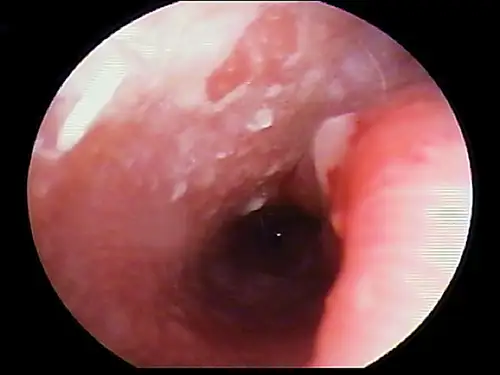

Any change in the epidermis, such as with ceruminous gland hyperplasia or ulceration, is significant and should be noted (Figure 4). In a patient with inflammatory ear disease, thickening of the epithelium may obscure visualization of blood vessels. The clinician should assess for presence of stenosis. Some dog breeds (eg, shar-peis, pugs) have small-diameter ear canals as part of their standard conformation. Differentiation between swelling and stenosis is necessary. Stenosis results from permanent pathologic changes within the epidermis of the ear canal (Figure 5).

FIGURE 4

Cerumen gland hyperplasia. Inflammation in the ear canal results in increased secretions from the apocrine glands, which enlarge above the epithelial surface.

For swelling of the ear canal caused by inflammation, it may be necessary to delay a complete examination of the ear canal until anti-inflammatory therapy (eg, systemic or topical corticosteroids) decreases the swelling.

If changes do not reverse, the prognosis for medical management is poor, and total ear canal ablation and/or bulla osteotomy is recommended. If the ear canal epithelium is smooth and pink in color but the ear canal diameter is narrowed, hyperplasia of the sebaceous glands may be present.